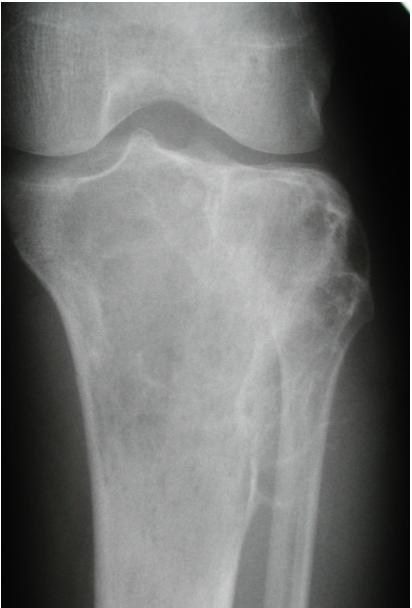

site: distal femur size: Most (involving how much? / cm?) matrix: mixed - mainly radiopaque , wide zone of transition, cortical destruction, resulted periosteal reaction, and codman’s triangle soft tissue involvement: